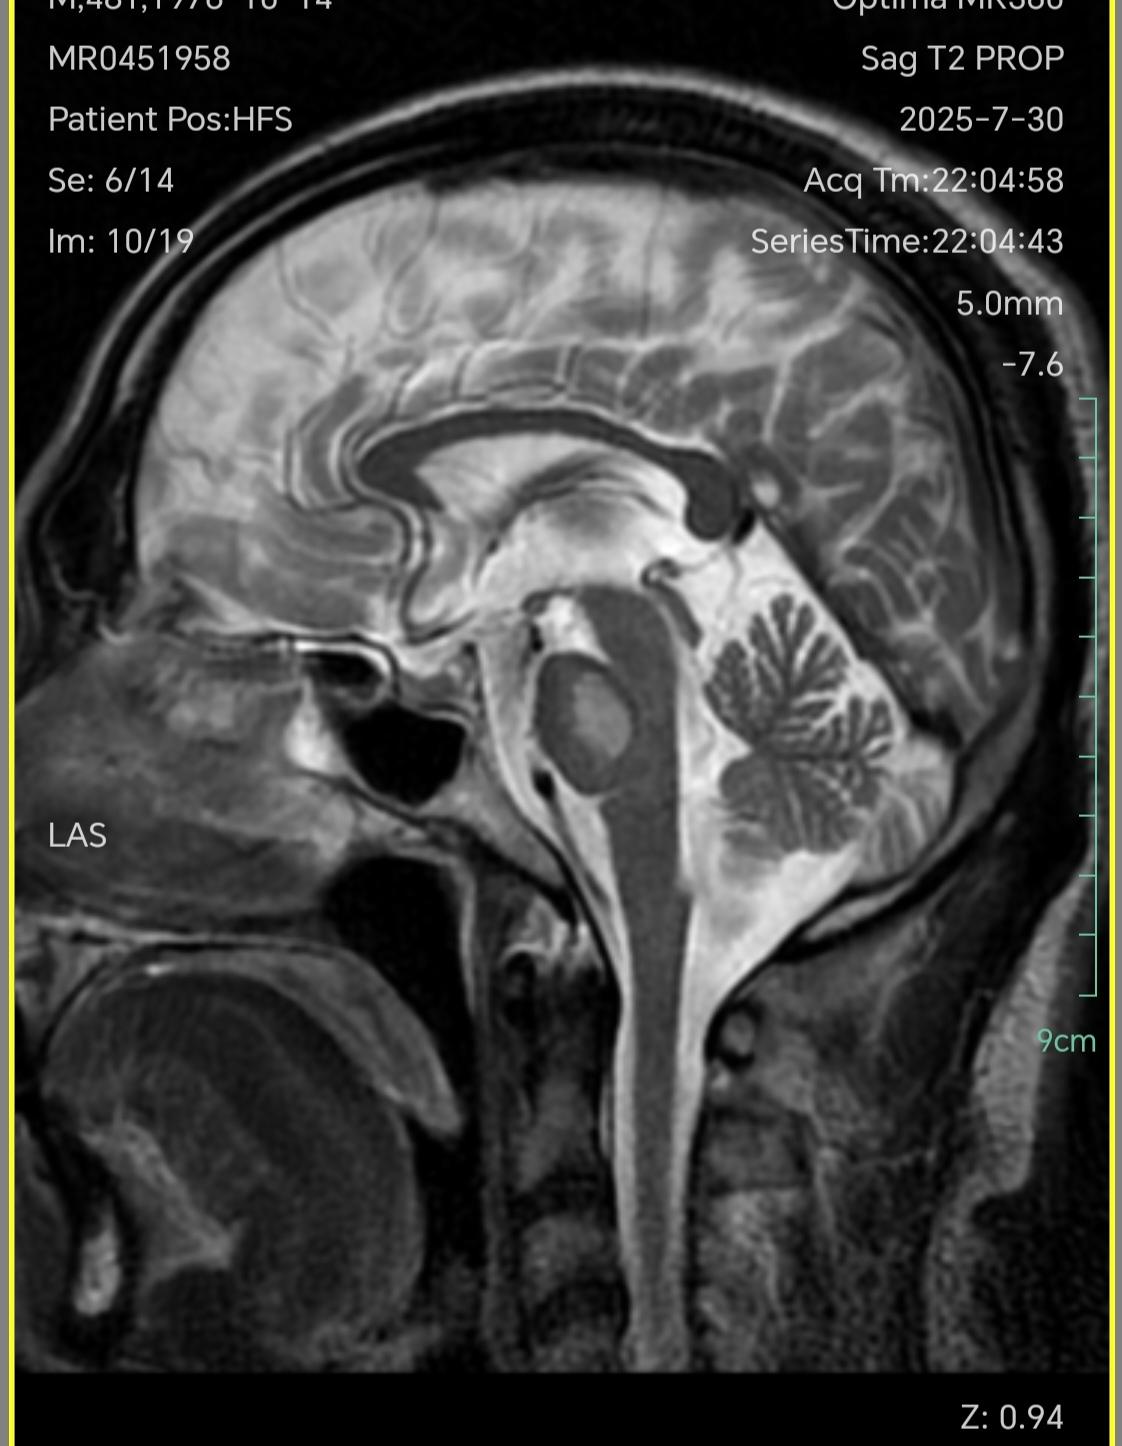

三叉戟🔱征。三叉戟征(Trident sign)是脑桥中央髓鞘溶解症较为典型的影像学表现,其形成的原因主要与该部位的解剖结构相关。中脑大脑脚的皮质脑桥纤维终止于脑桥核,这些细胞的轴突发出脑桥横行纤维,后者越过中线与皮质脊髓束和皮质核束交叉,并将其分成许多小束。脑桥横行纤维进入小脑中脚,分布于小脑半球。当这些部位的髓鞘溶解时,就可形成三叉戟征。